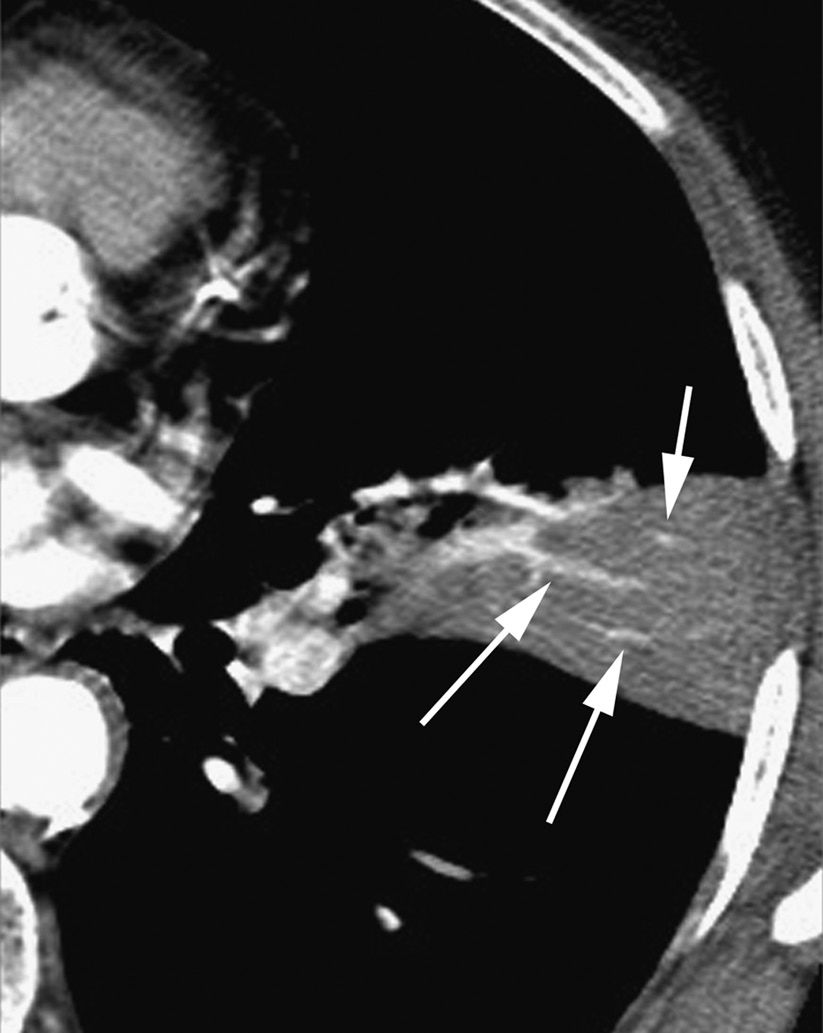

图2-4 实变,斑片状致密影

A、B. 支气管肺炎及小叶性实变患者增强HRCT显示单个小叶实变而周围邻近小叶正常,实变区小叶中心动脉( 白箭头) 和细支气管( 黑箭头);C. 冠状面CT 也显示斑片状实变影呈小叶性分布